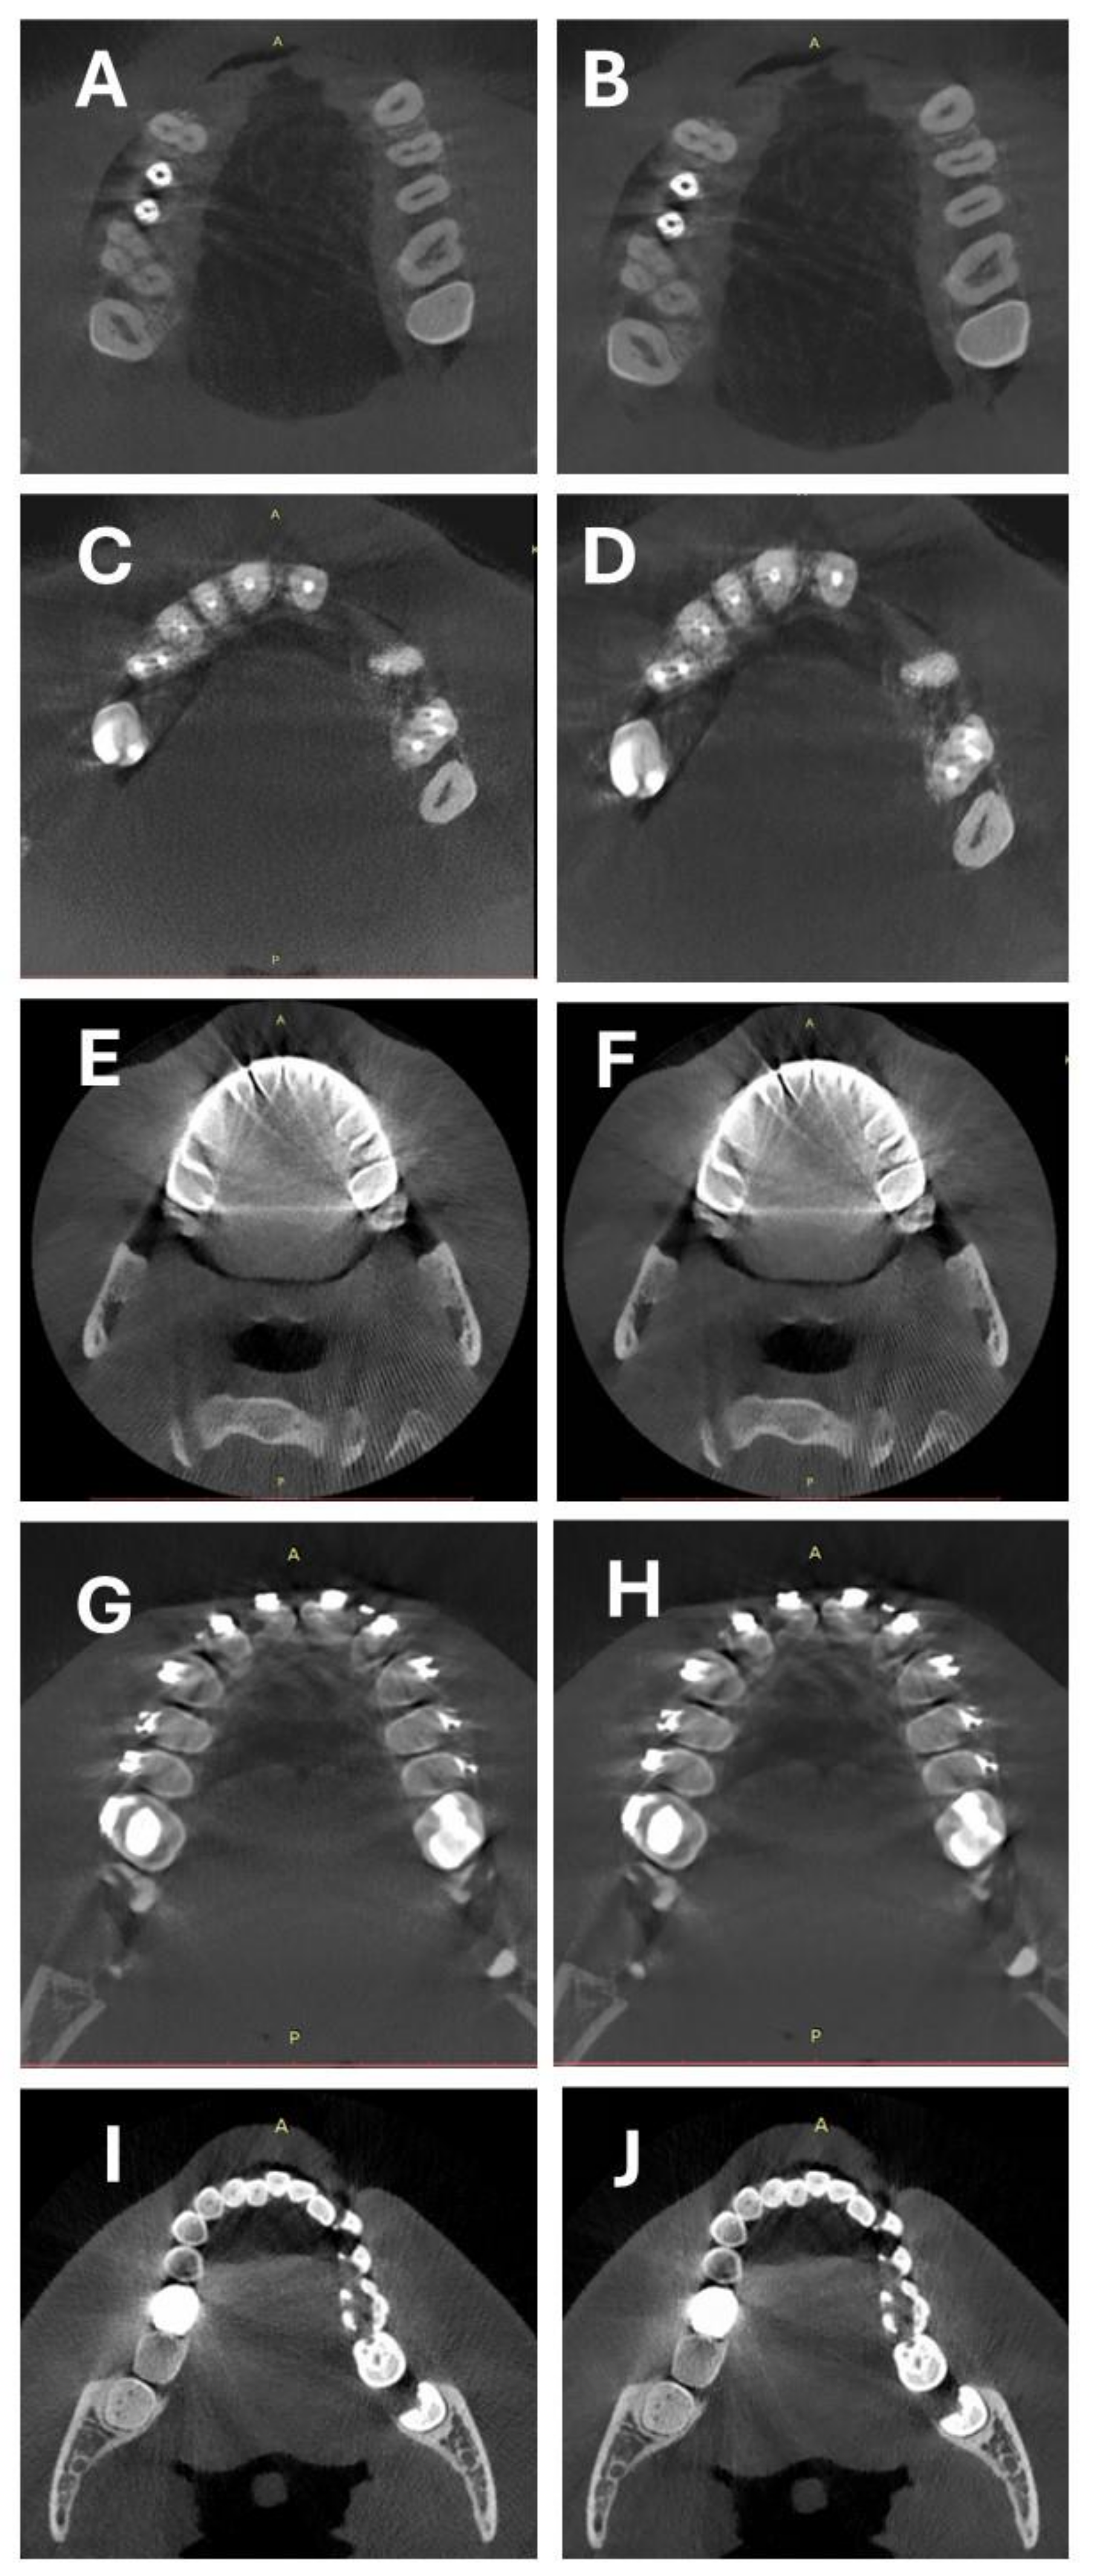

2.2. CBCT Scanning Protocol and Image Reconstruction

2.3. Objective Image Quality Assessment

2.4. Subjective Image Quality Assessment